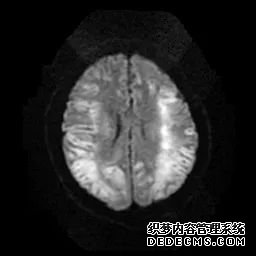

脑MRI显示尾状核、扁豆状核和脑梗头部T2/FLAIR呈双侧对称异常高信号。扩散限制涉及这些区域,其特征是扩散加权DWI(B-1000)上的高强度,ADC图上相应的减弱强度。

印象:通过将这些成像模式与临床和实验室检查结果相结合,就有可能得出低血糖性脑病。

影像影响内囊后肢、大脑皮层(特别是枕叶和岛叶)、海马和基底节区,常是双边对称性的。